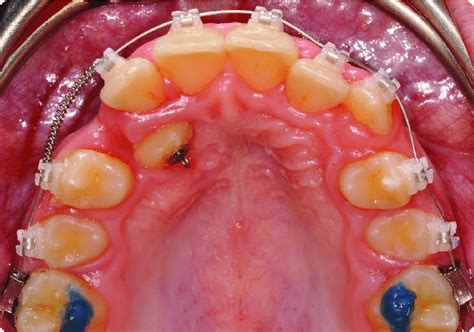

Figura 9 A) Vista intraoral, inmediatamente después de colocar aparatología fija multibrackets, tras retirar el aparato de Herbst.

B) Vista intraoral a las 48 h con el aparato funcional nocturno de contención colocado.

Cementamos aparatología fija multibrackets en ambas arcadas, con slot de .018" ´ .025" y la prescripción de Bench. Comenzaremos a nivelar las arcadas con arcos continuos primero, y luego con arcos de curva de Spee reversa en la arcada inferior y elásticos intermaxilares.